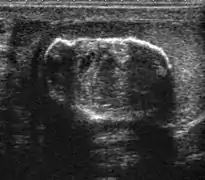

The incidence of infertility is decreased if surgical orchiopexy is carried out before the 1–3 years but the risk of malignancy does not change. Because of the superficial location of the inguinal canal in children, sonography of undescended testes should be performed with a high frequency transducer. At ultrasound, the undescended testis usually appears small, less echogenic than the contralateral normal testis and usually located in the inguinal region [Fig. 29]. With color Doppler, the vascularity of the undescended testis is poor.

Fig. 29. Undescended testis. (a) Normal testis in the scrotum. (b) Atrophic and decreased echogenicity of the contralateral testis of the same patient seen in the inguinal region.